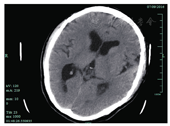

患者男,47岁,已婚。因头晕头痛伴记忆力减退2个月入院。患者于2个月前无明显诱因,出现阵发性头晕头痛,无恶心呕吐,休息后可缓解,记忆力减退,并逐渐加重,易怒,无其他不适。配偶梅毒血清学试验阴性。否认非婚性接触史及输血史。个人史、家族史无特殊。至杭州市第一人民医院心理科就诊,梅毒血清学试验结果:甲苯胺红不加热血清试验(TRUST)阳性(1∶32),梅毒螺旋体明胶凝集试验(TPPA)阳性,遂至皮肤科住院。患者于2016年7月6日行脑脊液检查:潘氏试验(+),白细胞计数9 × 106/L,蛋白74 mg/dl,TRUST阳性(1∶2),TPPA阳性,诊断为神经梅毒,麻痹性痴呆。7月7日,以青霉素钠针600万U,每6小时1次静脉滴注。7月9日凌晨青霉素静脉滴注结束5 min,患者突然倒地,左眼睑肿胀青紫,意识丧失,呼之不应,四肢抽搐,牙关紧闭,口吐白沫。血压198/104 mmHg(1 mmHg= 0.133 kPa),心率104次。查急诊头颅CT:提示两侧基底节区,侧室旁腔隙灶,两侧侧室、三室形态增大(图1)。患者癫痫症状持续30 min不能自行缓解。神经内科会诊诊断继发性癫痫,癫痫持续状态。7月12日,颅脑MRI平扫+弥散成像:两侧额顶枕部分皮层、丘脑区及侧脑室后角旁信号异常,考虑缺血性病变;两侧脑室增大表现。15日头颅CT平扫:左侧眶周软组织肿胀,左侧额窦后侧壁局部皮质断裂;两侧基底节区、侧室旁腔隙灶,幕上脑积水。余检查无明显异常。予安定、咪达唑仑、甘露醇及青霉素钠治疗下,患者仍呈持续浅昏迷状态,反复出现四肢抽搐。体检:右眼瞳孔直径3 mm,对光反射迟钝,左眼肿胀,对光反射无法配合,颈强直3指,左侧偏瘫,粗测肌力1级,左侧病理征阳性,右侧正常。余神经体检无法配合。2 d后转入神经内科,将青霉素钠改头孢曲松2 g每天1次静脉滴注治疗神经梅毒,予地西泮、丙戊酸钠、左乙拉西坦等进一步治疗癫痫。治疗2周后患者症状好转,意识清晰,四肢活动自如,反应仍迟钝,神经体检无特殊。出院后继续以苄星青霉素240万U肌内注射,每周1次,连续3次。3个月后随访,患者具备简单生活自理能力,但记忆力、计算力仍较差,未再出现癫痫。